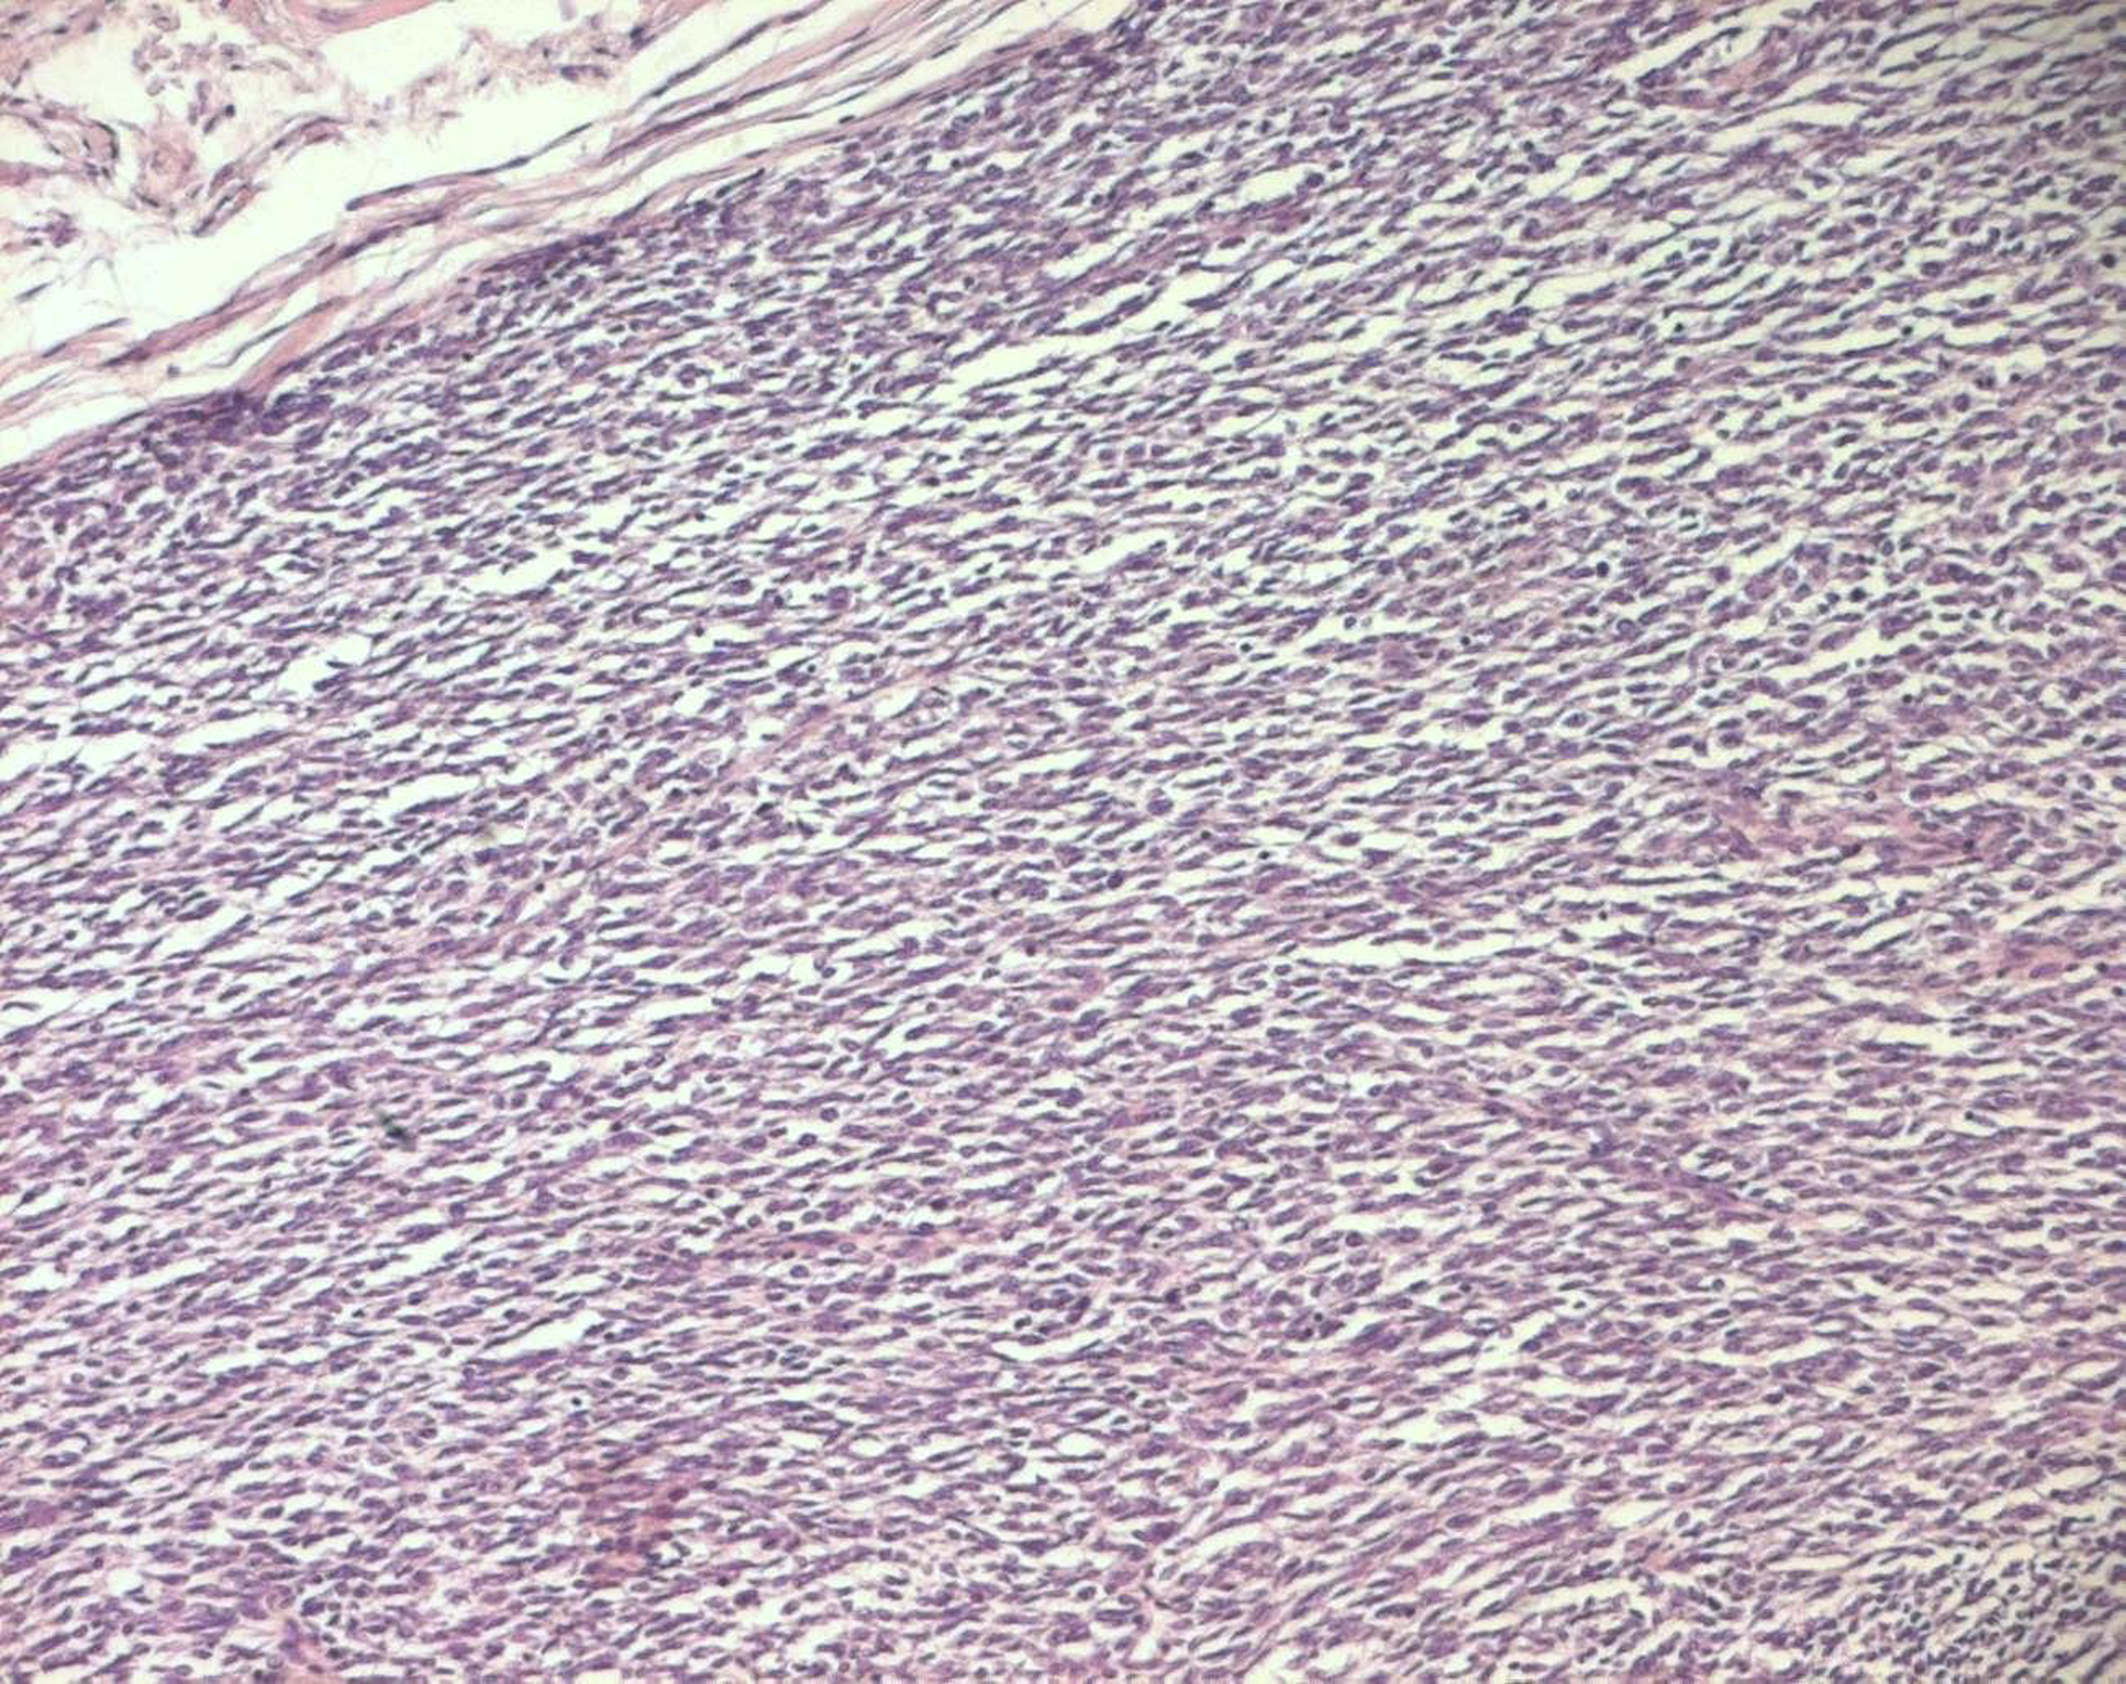

The histopathological study was performed on 8 surgical specimens and 4 biopsies. On gross appearance, tumors ranged in size from 3 to 17 cm (mean 8 cm), a diameter less than 5 cm was seen in only 3 cases. The tumors were soft or firm in consistency, grayish or whitish, well-circumscribed, encapsulated in 7 cases and showing cystic changes in 2 cases. Foci of necrosis were observed in 3 cases and macroscopic calcifications in 2 cases. On histological examination, calcifications were seen in 5 cases and foci of necrosis in 9 cases, osseous metaplasia was seen in one case. Histological subtypes included monophasic fibrous SS in 8 cases, biphasic SS in 3 cases and poorly differentiated SS in one case. There were no cases of monophasic epithelial SS. Monophasic fibrous SS showed a fascicular growth pattern with a variably collagenized stroma and a hemangiopericytoma-like vascular pattern (Fig. 3); biphasic SS showed, in addition to the abovementioned features, foci of glandular differentiation. Four tumors were grade 3 lesions and the 8 remaining cases were classified as grade 2 according to FNCLCC grading system. Immunohistochemically, the cases of biphasic SS were positive for Epithelial Membrane Antigen (EMA) and cytokeratin and negative for S100 protein and CD34. The cases of monophasic SS typically reacted at least focally with antibodies directed against EMA (Fig. 4), cytokeratin, vimentin and CD99. The poorly differentiated tumor had reactivity for S100 protein and vimentin and was negative for epithelial and muscular markers stains, it was otherwise morphologically and clinically compatible with the diagnosis of SS.

![]() Click for large image | Figure 3. Monophasic fibrous SS: fascicles of spindle cells (HE x 100). |